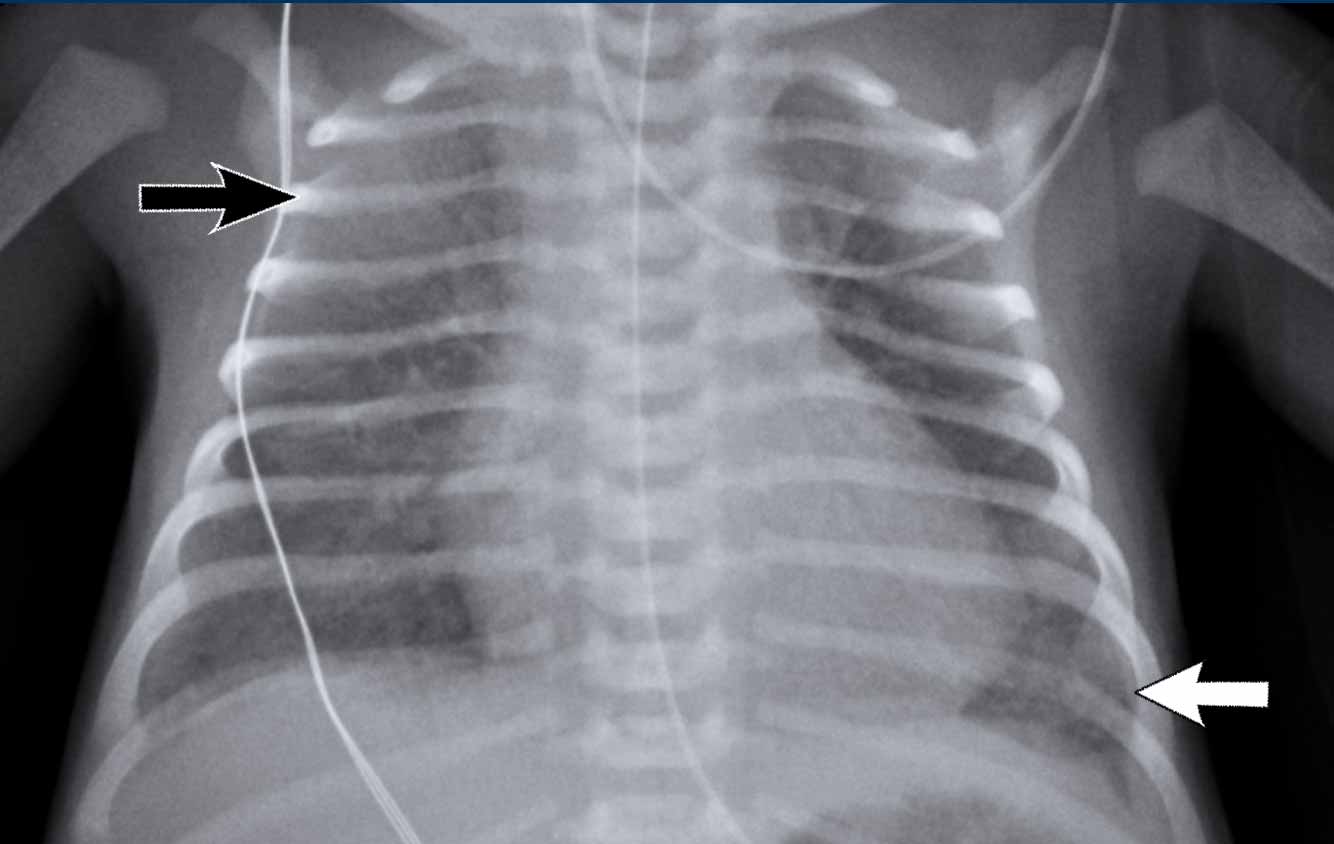

Jak rozpoznać zapalenie płuc na zdjęciu RTG u dziecka? Częściej multifokalne nacieki (do 50% przypadków wg wytycznych ESPID ), z mniejszą konsolidacją niż u dorosłych. W obrazie atypowym, np. chlamydialnym, dominują zmiany dolno-płucne z perihilar thickening. Radiolog stosuje skalę Radiographic Assessment of Lung Edema (RALE) do kwantyfikacji – punktacja powyżej 12 wskazuje ciężki przebieg. (Nawiasem mówiąc, w erze AI algorytmy jak CheXNet wykrywają je z 92% czułością). „Złoty standard” to nadal wizualna analiza przez specjalistę.